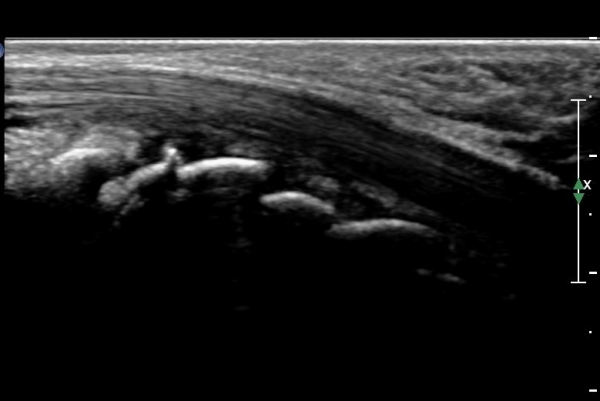

¼Õ¸ñ ÀåÃø Á¾´Ü¸é°Ë»ç¿¡¼­ ¿ù»ó°ñ °ñ±ØÀÌ °üÂûµÊ(»çÁø 2).